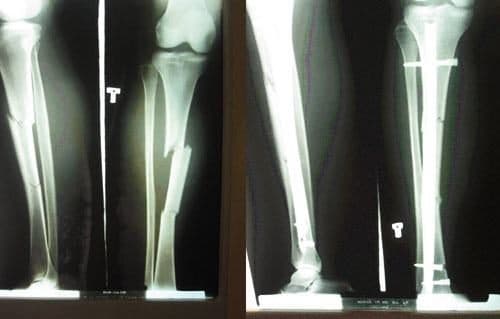

Phẫu thuật gãy xương đòn Tại Bệnh viện Thu Cúc

Phẫu thuật gãy xương đòn giúp nắn chỉnh xương gãy ngay ngắn và cố định xương gãy ở vị trí tốt nhất trong khi chờ xương lành. Bệnh viện Đa khoa Quốc tế Thu Cúc là một trong những địa chỉ phẫu thuật điều trị gãy xương đòn uy tín tại Hà Nội, được đông […]